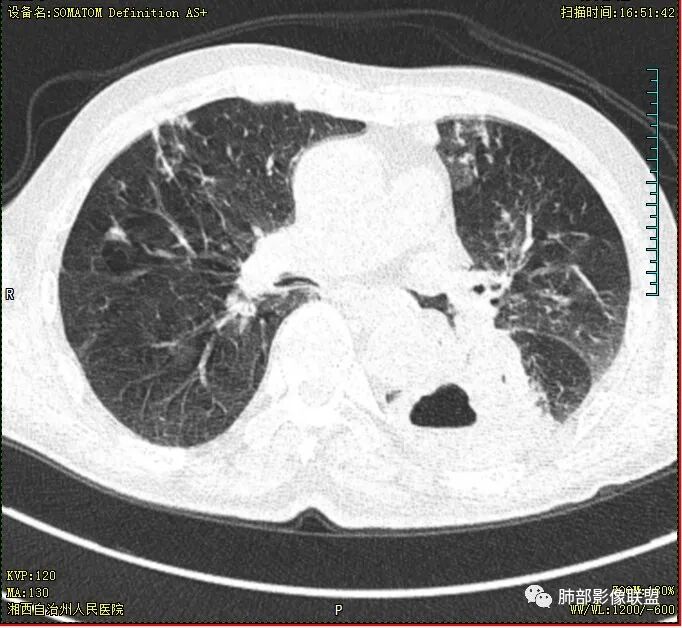

晨读 双肺多发斑片、斑点影,可见树芽征,支气管播散,右肺上叶小空洞,左肺下叶厚壁空洞,内壁较光整,有浅液平,右下叶背段支气管变窄,不均匀强化。结合临床考虑结核并感染,待排除合并肺癌可能。

晨读:老年男性患者,痰中带血伴间断发热2周,体温39.4℃,白细胞、中性粒细胞,CRP增高,Tspot阳性,胸部CT:双肺病变,左肺下叶背段大片实变密度影,边界模糊,内部见空洞形成,空洞内壁总体光滑,有气液平,增强扫描轻度不均匀强化,一月后复查空洞消失,实变影吸收减少,考虑感染性病变,结核伴肺脓肿。

晨读,老年男性,中等病程,咳嗽,痰中带血,发热,主病灶位于左肺下叶空洞,厚壁,偏心,内壁光滑,边界清楚,不均匀强化,内有坏死,考虑结核,内有气液平,周围部分小叶中心结界,好热,白细胞升高,合并感染。结核合并感染,鉴别肺癌合并感染。

老年慢性长期吸烟,痰中带血伴发高热。左下肺大片不均质实变里可见一含气液平厚壁空洞,内壁有坏死物残留,增强可空洞壁明显强化轮廓显示清晰,空洞位于肺门侧,近端支气管壁不规则增厚。两肺散在斑片状影,并见小树芽。18号复查肺窗空洞显示不清,20号用了俯卧位扫描,液体向下流动空洞又显示出来了。左下肺病灶有变小,还是考虑感染性病变,结核合并感染,鉴别鳞癌。

老年患者。左肺下叶厚壁空洞,有液平面。空洞内壁较为光整。病灶的内侧见支气管节段性的变窄扭曲。两肺内,弥漫性的广泛性的播散病灶。考虑感染性病变。肺结核并空洞形成两肺内播散。鉴别诊断-左肺下叶鳞癌。

双肺多发结节影,树芽征,小叶中心分布,左肺下叶不规则空洞,洞内壁光滑,见液平,洞壁似与支气管相通,增强扫描明显强化,可见血管造影征。三周左右复查空洞明显缩小。

双肺多发点片、索条斑条灶,见多发树丫征,左下肺大片不均质实变,内见一含气液平厚壁空洞,壁厚,内壁有坏死物残留,增强可空洞壁明显强化

,空洞位于肺门侧,近端支气管壁不规则增厚。

胸部CT:双肺多发小斑片、树芽、索条灶,左下肺大片不均质实变,远肺门侧厚壁空洞,气液平,内壁有坏死物残留,增强可空洞壁不均匀强化,近端支气管壁不规则增厚堵塞,实变影内可见与洞壁平行支气管。抗炎3周有缩小。

双肺边界较清楚的斑点状影、树芽征,结合T-SPOT阳性,长病程,体重减轻等,继发性肺结核是应当考虑的,至少作为基础疾病之一。